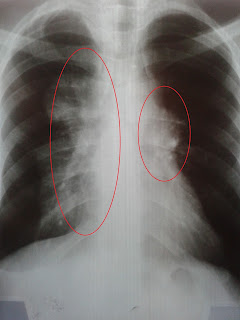

Esta foi a primeira radiografia,  feita a pedido de um médico da Casa de Saude, de maneira rude mas necessária ele questionou na época "esse é o seu pulmão? Acho que você gosta pouco de você hein! "

Bom, eu não fumo, eu não tinha o diagnostico, não sabia de nada do que estava acontecendo, apenas estava com tosse, e demorei um bocado pra ir ao médico. Achei um pouco exagerado. Mas enfim as regiões brancas são as areas afetadas pelos tumores.